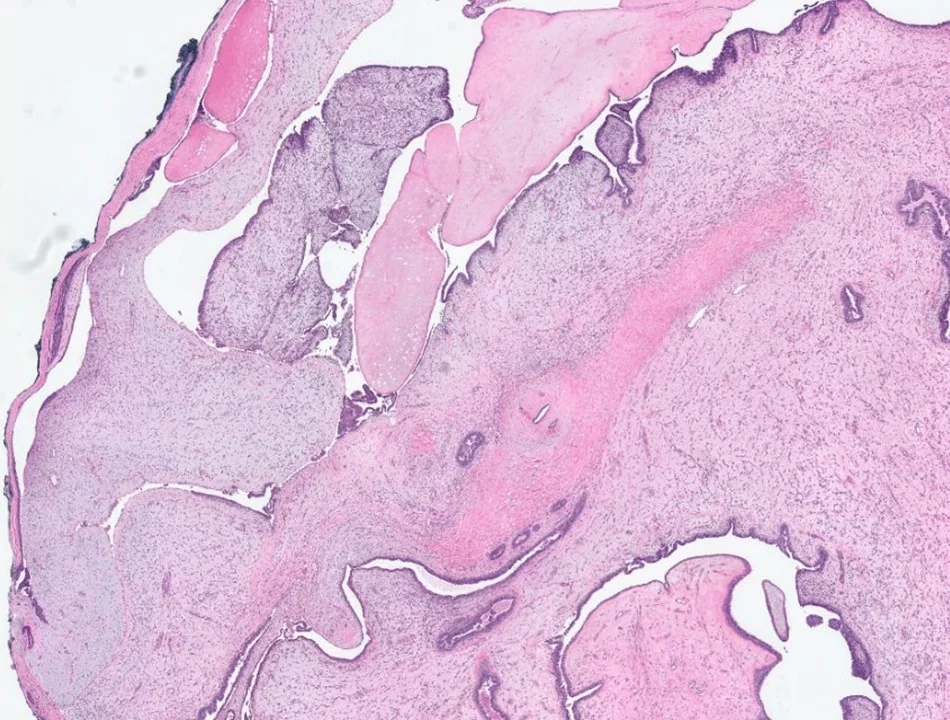

Paget Disease of Nipple

Found in less than 5% of patients with breast cancer. Characterized by malignant glandular epithelial cells scattered within the nipple epidermis.

Paget Disease of Nipple - cytokeratin 7 immunostain

Paget cells with show expression of LMW cytokeratins (such as CK7). Will also commonly show expression of HER2.